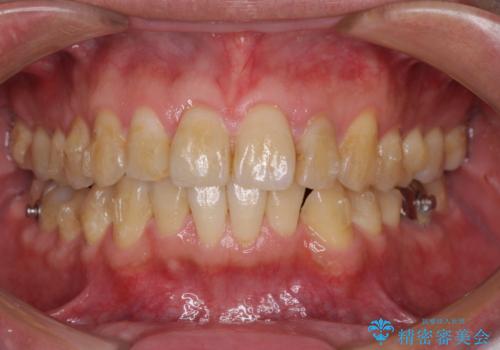

前歯のデコボコと下顎の八重歯 インビザラインによる矯正治療

- 前歯のデコボコや八重歯を気にして来院された患者様です。

インビザラインを用いて、歯列を整えることとしました。